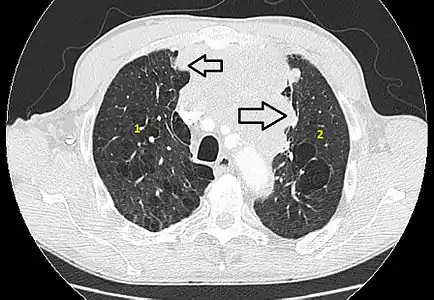

6 : sternum. Scanner en fenêtre parenchymateuse, montrant un carcinome thymique envahissant les poumons (avec des lésions d'emphysème) au contact des deux poumons (1 : poumon droit ; 2 : poumon gauche) ;

Scanner en fenêtre parenchymateuse, montrant un carcinome thymique envahissant les poumons (avec des lésions d'emphysème) au contact des deux poumons (1 : poumon droit ; 2 : poumon gauche) ;

flèches noires : zones suspectes d'envahissement.